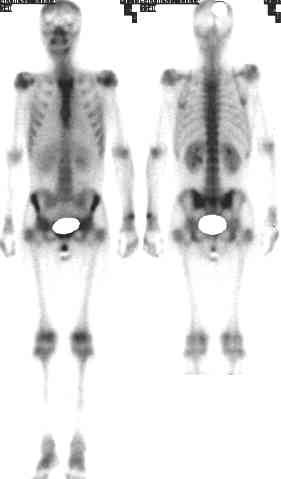

Si has dado con esta

web, probablemente es porque has sido diagnosticado de Osteomielitis.

Esta es una enfermedad que no te matará, pero es muy probable que

su tratamiento sea muy largo, e incluso puede que tengas que convivir

muchos años con ella.

Debes saber que la posible

curación de esta enfermedad pasa por un proceso largo y doloroso,

con cirugías muy agresivas. Es posible que la medicina no logre

vencer la infección y ésta se convierta en crónica.

Si el hueso está consolidado, podrás caminar con relativa

comodidad y el mantenimiento de la fístula no te ocupará

mas de 10 minutos al dia.

En este estado es muy importante la higiene y prevenir posibles fracturas,

mediante el uso de una ortesis a medida en las situaciones de riesgo.

Si sufres una refracturación, es posible que derive en pseudoartrosis,

muy dificil de tratar en estas circunstancias, lo que te obligará

a valorar la posibilidad de amputarte.